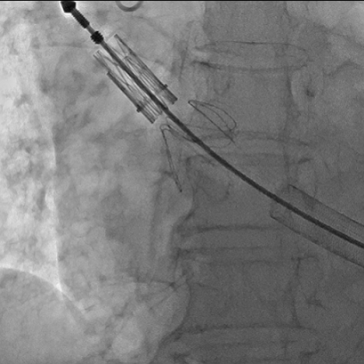

经右侧股静脉置入临时起搏器,经右侧股动脉在患者主动脉无冠窦内放置1根6F猪尾导管协助定位。透视下定位后第五肋间小切口进胸,打开心包,选择心尖裸区缝制六边形荷包。心尖穿刺后将泥鳅导丝过主动脉瓣经升主动脉、主动脉弓到达降主动脉膈肌水平(图1),通过TEE确认细导丝没有与二尖瓣腱索缠绕。单弯管交换硬导丝后(图2、图3),用16F扩张鞘预扩心尖穿刺处,后将 J-Valve瓣膜(29mm)装入输送器。将输送器推送至主动脉根部,释放定位件,适当调整定位件角度使其进入三个主动脉窦部,并通过DSA和TEE确定三个定位件准确入窦后完全释放瓣膜,撤出输送器(图4)。通过DSA和TEE观察人工瓣膜膨胀后金属支架的形态、位置良好,无瓣周漏,收缩期左室侧反流消失(图5、图6)。撤出导丝,收紧心尖处荷包线并打结,后鱼精蛋白中和肝素,彻底止血,逐层关胸,封皮,拔出股动脉鞘并在股动脉穿刺处压迫止血。手术过程顺利,患者生命体征平稳。

图2 单弯管进入左室、升主动脉内

图3 主动脉瓣大量反流;主动脉瓣环平面几乎与脊柱平行